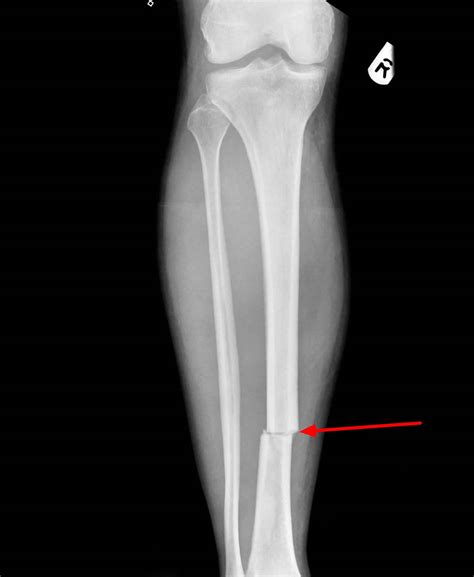

• Imaging Studies: X-rays are the primary imaging modality used to visualize the fracture. In some cases, CT scans or MRI may be required for a more detailed assessment.

Case Study 1: A 30-year-old athlete sustains a transverse fracture of the tibia during a soccer match. The fracture is diagnosed through X-rays, and the athlete undergoes surgical treatment with ORIF. Post-operative rehabilitation includes physical therapy to restore strength and mobility.

• transverse fracture x ray

• transverse fracture description